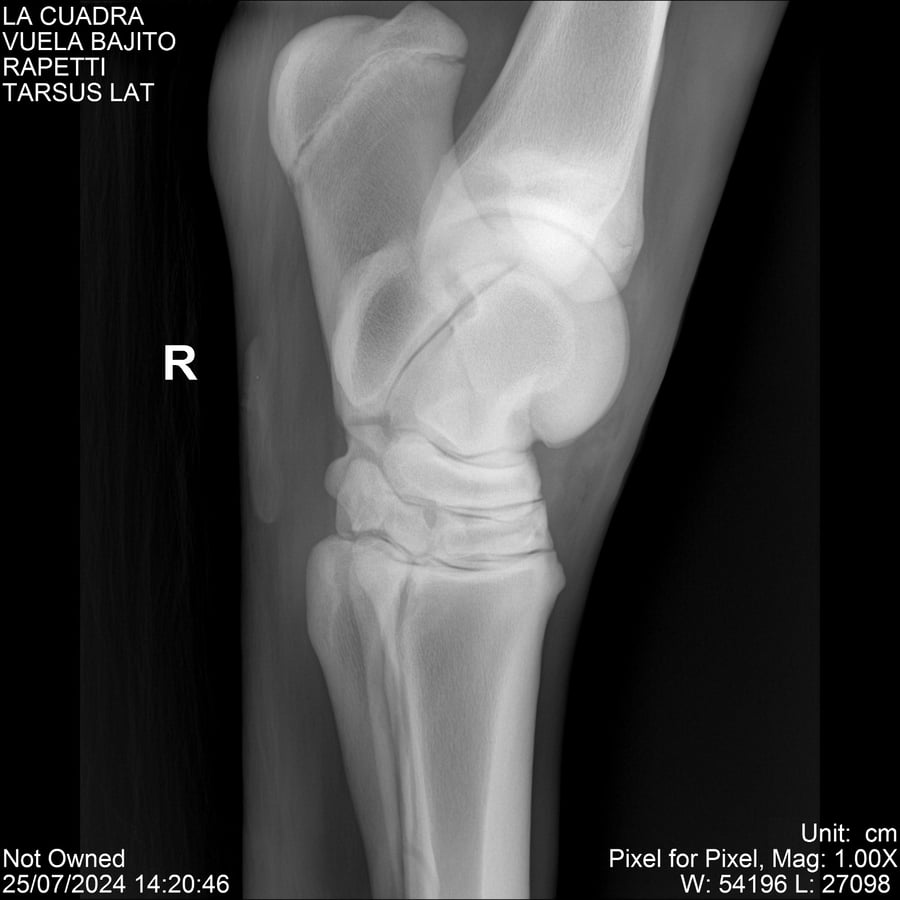

LOTE 16, VUELA BAJITO Lote Anterior Volver al remate Lote Siguiente Ficha Contacto Montevideo - Ficha del Lote Identificador: #284451 Categoría: Yeguarizos Montevideo - 77 Visualizaciones ClicData Contacto Empresa: Abelenda N. R., Walter Hugo Nombre*: Teléfono* : E-mail* : Mensaje Enviar Registrese gratis Este contenido Exclusivo está disponible sólo para usuarios registrados Ingresar